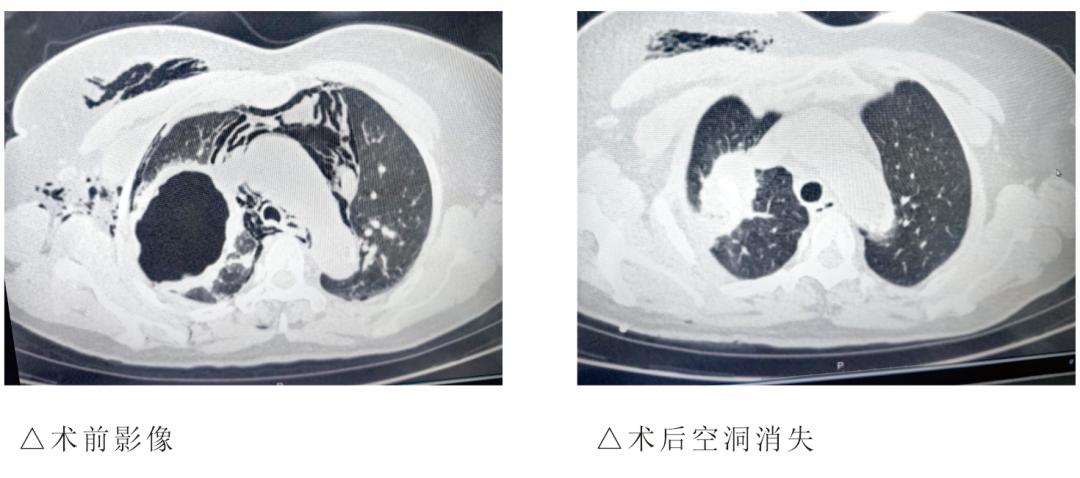

胸部CT检查显示,张阿姨右侧气胸,右肺上叶有一个7.4cm×5.5cm的空洞,颈部、胸壁甚至右侧腋窝都有多发积气,情况十分危急。医生立即为她进行胸腔闭式引流治疗,但漏气问题始终没有解决,病情迟迟不见好转。

整个手术无需开胸,创伤极小,全程顺利。术后,张阿姨胸腔引流的漏气量逐渐减少,最终完全停止,颈部、胸壁的皮下气肿慢慢吸收,胸闷、气促的症状也明显改善,经过观察和护理,病情稳定后顺利出院。